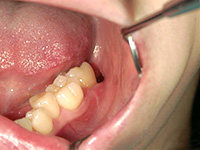

結合組織移植術

右上3番、4番の歯の根が露出していたため、上顎の裏側から結合組織を移植しました。

他の箇所とかわりなく、きれいな歯ぐきになりました。

上顎裏側の結合組織を摘出しています。術後の傷も、きれいに治りました。